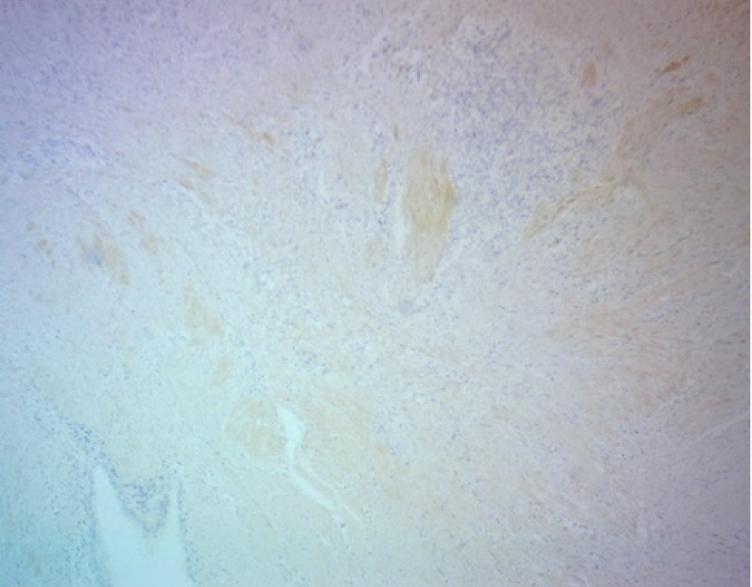

При гистологическом исследовании операционного материала во всех наблюдениях, независимо от органной локализации, патологический процесс характеризовался типовой для эндометриоза гистологической картиной: сочетанием желез, выстланных однорядным эпителием эндометриального типа с эндометриальной цитогенной стромой, вариабельной частотой кровоизлияний, отложением гемосидерина. Эндометриоидные гетеротопии имели преимущественно эпителиально-стромальное строение, очаги стромального эндометриоза встречались редко. В большинстве наблюдений эндометриоидные гетеротопии были множественными, размеры их варьировали от 1 до 2 полей зрения при луповом увеличении микроскопа. Эпителиальный и стромальный компоненты эндометриоидных гетеротопий характеризовались разнообразием морфофункциональных проявлений в виде пролиферации, секреции, кистозной трансформации желез с атрофией и/или десквамацией эпителия, подобно изменениям в эутопическом эндометрии в зависимости от фазы менструального цикла. Особенности и варианты морфофункциональных изменений в гетеротопиях зависели от органной локализации процесса. Для эндометриоза передней брюшной стенки характерной была выраженная тенденция к кистозной трансформации эндометриальных желез с атрофией и/или десквамацией эпителиальной выстилки. При поражении различных отделов кишечника в очагах эндометриоза обнаруживали преимущественно пролиферативные изменения в эпителиальном и стромальном компонентах гетеротопий. Независимо от органной локализации заболевания, в цитогенной строме очагов эндометриоза и в окружающих их тканях была обнаружена лимфо-макрофагальная инфильтрация различной степени выраженности, наибольшая − в местах отложения гемосидерина. В некоторых случаях выявлялась очаговая лимфо-макрофагальная инфильтрация по типу микроабсцессов. В таких инфильтратах встречались гигантские многоядерные клетки, присущие продуктивному воспалению и гранулемам инородных тел. Вокруг очагов эндометриоза и между ними было обнаружено разрастание «полей» соединительной ткани с большим количество коллагеновых волокон. Такая особенность в большей степени была присуща эндометриозу передней брюшной стенки, промежности и легкого (рис. 1, 2). При эндометриозе различных отделов кишечника площадь пролиферации соединительнотканных волокон вокруг гетеротопий была значительно меньше.

ИГХ-исследование выявило положительную экспрессию гладкомышечного актина в фокусах фиброза вокруг и между очагами экстрагенитального эндометриоза. Гладкомышечный актин экспрессировался в миофибробластах, концентрически расположенных вокруг эндометриоидных гетеротопий по типу «муфт» (рис. 3).